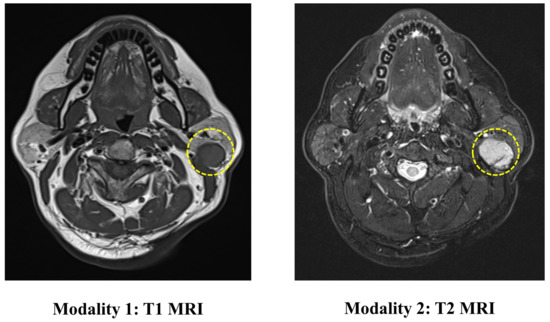

The PGT dataset contains 344 head and neck MRI examinations carried out at the Stomatological Hospital of China Medical University. The ethics board approved the use of the images for this research. This dataset includes two modalities of MRI (T1 and T2), as shown in Figure 4. The ground truth labels are obtained from biopsies.

Figure 4. An illustration of the images in the PGT dataset. The yellow circle represents the location of the tumor.